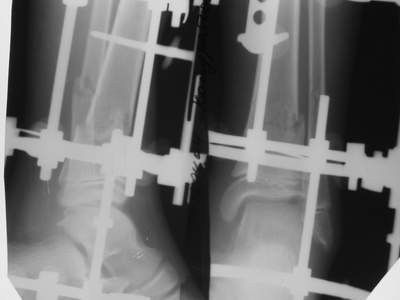

Вытяжение

1) з/репозиция, 2) фиксация 2 спицами, 3) аппарат, 4) фиксационные

спицы удалены...

См. аттачт.